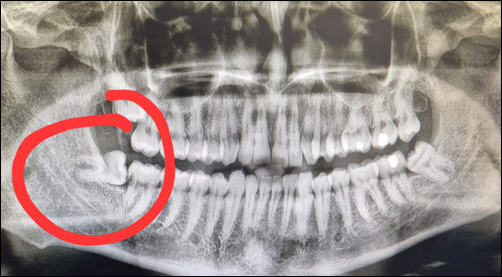

Wisdom teeth can cause a range of issues, especially if they are impacted, meaning they don’t fully emerge through the gum line. Impacted wisdom teeth can push against other teeth, leading to crowding, pain, or damage to adjacent teeth. Additionally, these teeth can trap bacteria and food, increasing the risk of infection, cysts, or decay. Dentists often recommend removing them proactively to prevent future complications.

Before the procedure, your dentist or oral surgeon will review your medical history, take x-rays, and explain what to expect. They’ll go over anesthesia options, which typically include local anesthesia, sedation, or general anesthesia, depending on the complexity of the extraction and your comfort level. You’ll want to arrange for a ride home afterward, as the anesthesia may leave you groggy or drowsy.